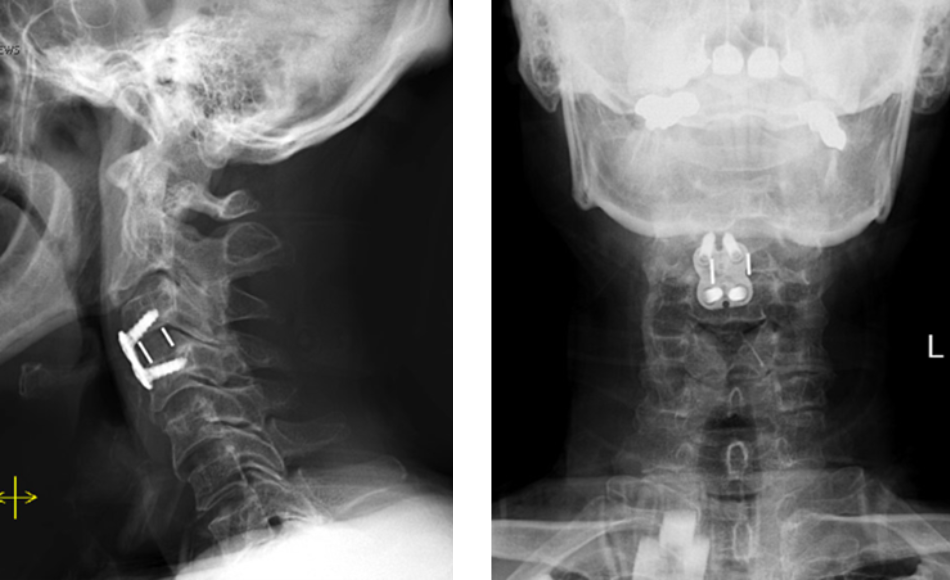

Back:

Revision Surgery Treats Intractable Neck Pain & Cervical Deformity

Author: Benjamin R. Cohen M.D., F.A.A.N.S., F.A.C.S., Read More!

Spine:

Cervical Laminectomy and Fusion

Author: William Sonstein M.D., F.A.C.S., Read More!